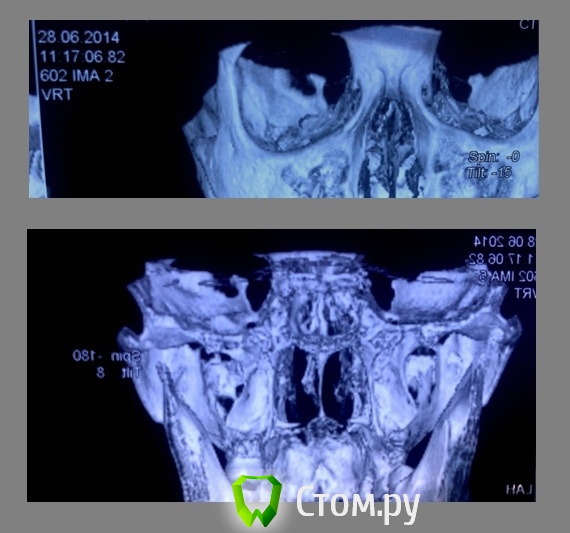

Василь Опубликовано 2 июля, 2014 Автор Поделиться Опубликовано 2 июля, 2014 (изменено) сегодня был у дока. он говорит с правой стороны перелом, у него еще снимок есть только другой с затылка что ли) да и боли были справа.Мол а справа просто снимок затемнился. говорит 21 июля, если все будет нормально, то может снимут шину, и сделают повторный снимок.( хотя мол он вряд ли что то покажет) А точно удалять придется 38? Тот же хирург сказал, что если не будет беспокоить то можно не трогать 38, как и верхние. Изменено 2 июля, 2014 пользователем Василь Ссылка на комментарий

kriokov Опубликовано 2 июля, 2014 Поделиться Опубликовано 2 июля, 2014 (изменено) топикстартеруВас боли, отек, боли при жевании с какой стороны беспокоят, справа?Иммобилизация челюсти в любом случае для Вас показана.Ну и снимки новые не повредят, как уже сказали Ну покажите мне линию перелома коллеги . . .то же не увидел. Сравнивал кортикальную канала, он вроде четко виден, нигде не прерывается, и не смещается. Изменено 2 июля, 2014 пользователем kriokov 1 Ссылка на комментарий

kriokov Опубликовано 2 июля, 2014 Поделиться Опубликовано 2 июля, 2014 страшного ничего, но другой снимок нужен Ссылка на комментарий

Maxfac Опубликовано 2 июля, 2014 Поделиться Опубликовано 2 июля, 2014 По поводу информативности снимка выше уже отписался рентгенолог. А механизм травмы какой? Ссылка на комментарий

Василь Опубликовано 3 июля, 2014 Автор Поделиться Опубликовано 3 июля, 2014 По поводу информативности снимка выше уже отписался рентгенолог.А механизм травмы какой?Удар, Видимо рукой. Ссылка на комментарий